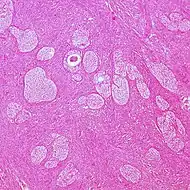

| Adult granulosa cell tumor | 1% | Almost 100% | Small, bland, cuboidal to polygonal cells in various patterns.[20] | ![]() | ||